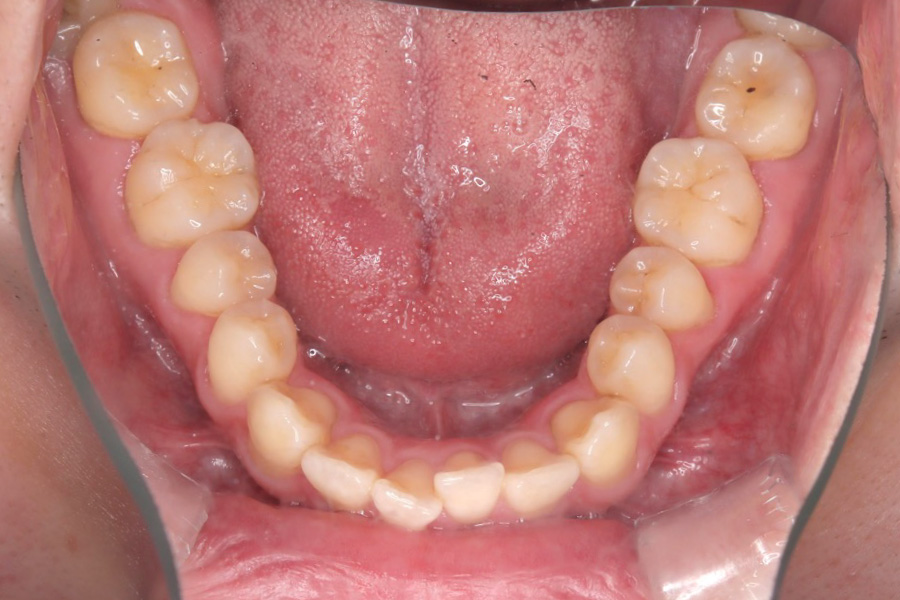

治療後

主訴 歯のガタつき

期間 1年半

治療内容 インビザライン矯正

非抜歯